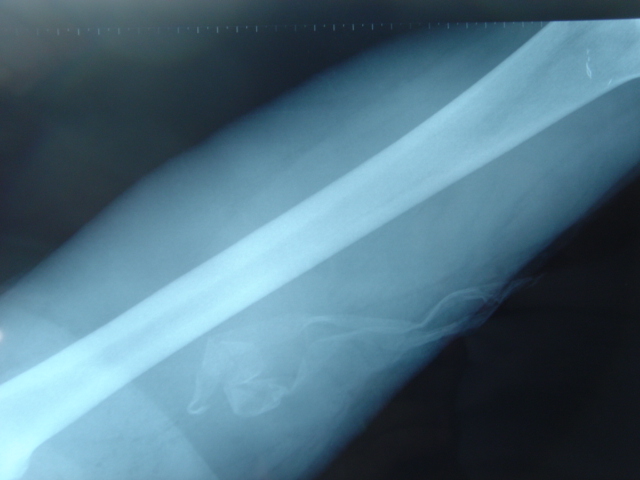

A Rx. se ven perfectamente los drenajes y se puede calibrar la longitud.